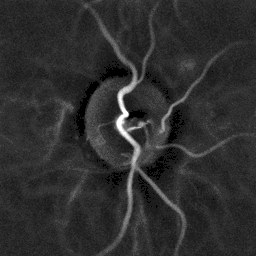

Laser Doppler imaging of the papilla of a patient with hypertension]]

Fundoscopy and patients history.